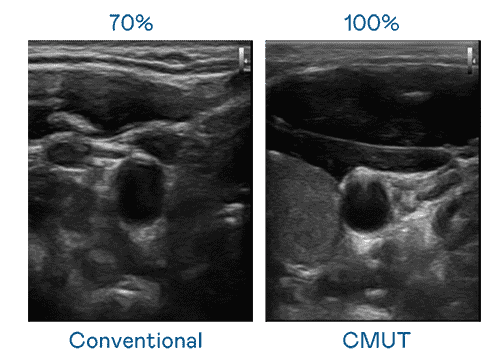

CMUT 技术是一种用电容式微机电元件来产生超音波讯号的技术。。。与传统 PZT 压电式技术相比,,,CMUT 频宽增加 30%,,更宽频的超音波讯号让影像解析度大幅提升,,,是实现高影像品质医疗超音波扫描、、、促进精准医疗发展的关键技术。。。

大频宽带来超清晰影像

超音波影像的解析度高低,,,,首先取决于探头能发出的讯号频宽。。。YAXIN111 CMUT 可提供高清晰的超音波讯号,,,,提供高频宽、、高灵敏度、、影像纹理细节更高的超音波影像,,,协助医护人员缩短影像判读时间及利用精准的医疗影像进行诊断。。。